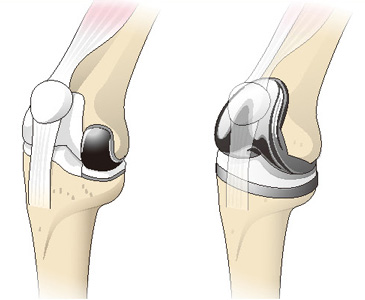

最新デザインの 膝関節の難治性病態に対する手術―日常診療で困ったときのこの一 医学一般